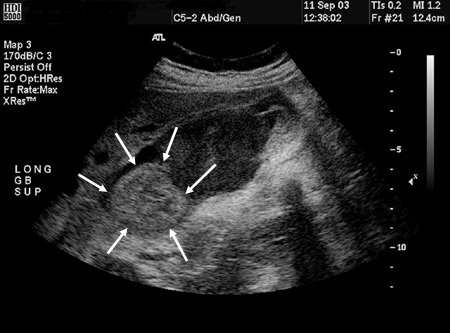

Colangiocarcinoma

Ultrassonografia da vesícula biliar com massa (setas)

Do acervo de Dr. Joseph Espat; usado com permissão